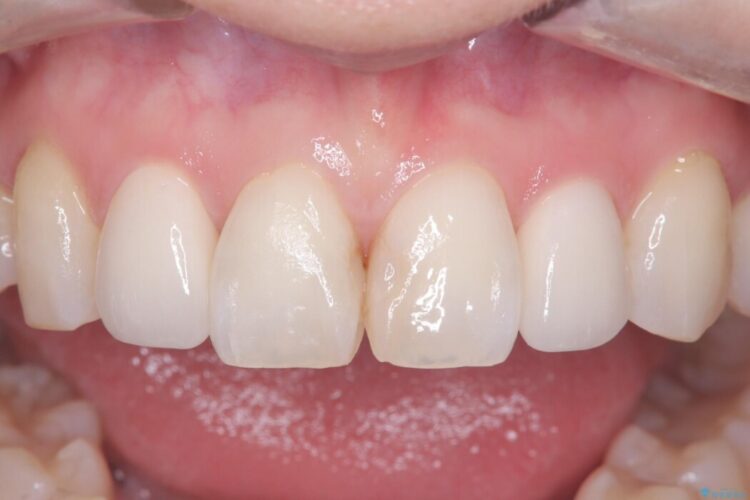

欠けて変色した前歯をオールセラミックで美しく

欠けて変色した前歯をオールセラミックで美しく ビフォー 欠けて変色した前歯をオールセラミックで美しく アフター

上の前歯4本が、過去の治療による変色や欠けで見た目が気になるとご来院されました。